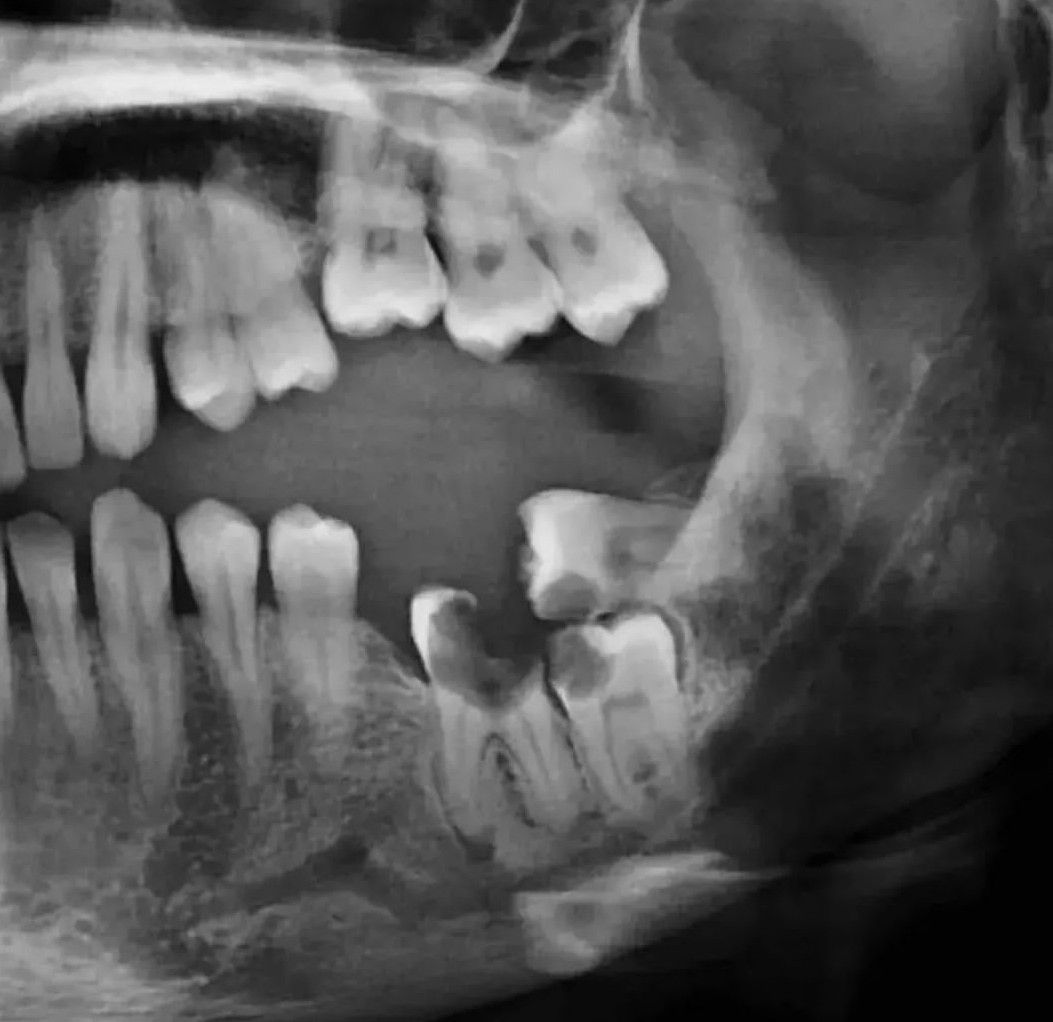

Interprete the OPG

How many pathologies can you locate?